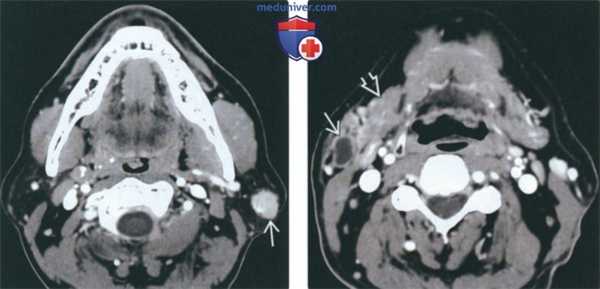

• Присутствует шейная лимфаденопатия![КТ, МРТ при опухоли Вартина]()

(Слева) КТ с КУ, аксиальная проекция. В поверхностной доле околоушной железы имеется круглое образование, равномерно накапливающее контрастное вещество. Мелкие опухоли Вартина могут накапливать контраст равномерно, но крупные новообразования обычно характеризуются неоднородным накоплением контрастного вещества.

(Справа) КТ с КУ, аксиальная проекция. Латеральнее поднижнечелюстной железы, в области хвоста околоушной железы, имеется кистозное образование. В большинстве случаев опухоль Вартина возникает в пределах самой железы, однако некоторые новообразования прорастают из окружающих лимфатических узлов.г) Патология:

• Шейная лимфаденопатия помогает отличить лимфому от опухоли Уортина![КТ, МРТ при опухоли Уортина]()

(Слева) На аксиальной КТ с КУ в поверхностной доле околоушной железы визуализируется округлая опухоль, равномерно накапливающая контраст. Маленькие опухоли Уортина могут контрастироваться равномерно, в то время как для больших в целом характерно неравномерное накопление контраста.

(Справа) На аксиальной КТ с КУ возле хвоста околоушной железы визуализируется кистозное образование снаружи от поднижнечелюстной железы. Хотя большинство опухолей Уортина возникают в околоушной железе, некоторые могут обнаруживаться и в перипаротидных лимфоузлах.1. Общая характеристика: